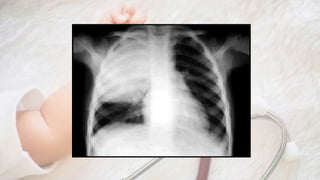

• Rx: atrapamiento aéreo, hiperaireación pulmonar y, con menor

frecuencia, infiltrados perihiliares y atelectasias laminares o

segmentarias

• Ocupación de espacios aéreos terminales: consolidación lobar,

segmentaria o subsegmentaria del parénquima

• Abombamiento de cisuras: neumonia por K. pneumoniae

• Coexistencia de espacios terminales ocupados y vías aéreas libres:

broncograma aéreo

• Imagen única en un segmento o lóbulo: neumonía bacteriana

neumocócica (niño mayor)

• Neumonía redonda u oval, fase inicial de neumococias en niño pequeño

• Bronconeumonía: sombras parcheadas (atelectasia) y/o hiperclaridades

(atrapamiento aéreo). Infiltrados perihiliares o difusos y opacidades de

múltiples focos parenquimatosos de consolidación

• Neumonía intersticial: infiltrado hiliar bilateral, hilios mal definidos,

desdibujan la silueta cardiaca (“corazón velloso”) o mayor extensión

hiliofugal (“alas de mariposa”)

• Neumonías víricas o por M. pneumoniae, gesticulación fina o mediana

difusa, segmentaria o lobar, con aspecto de vidrio deslustrado